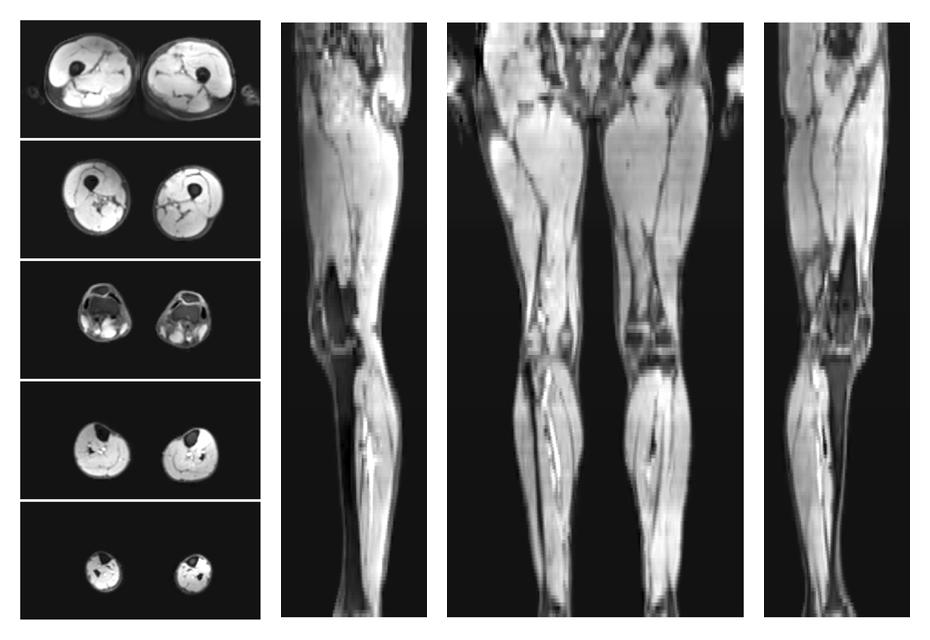

• Water only signal

The water part of the acquired multi-echo spin echo data.